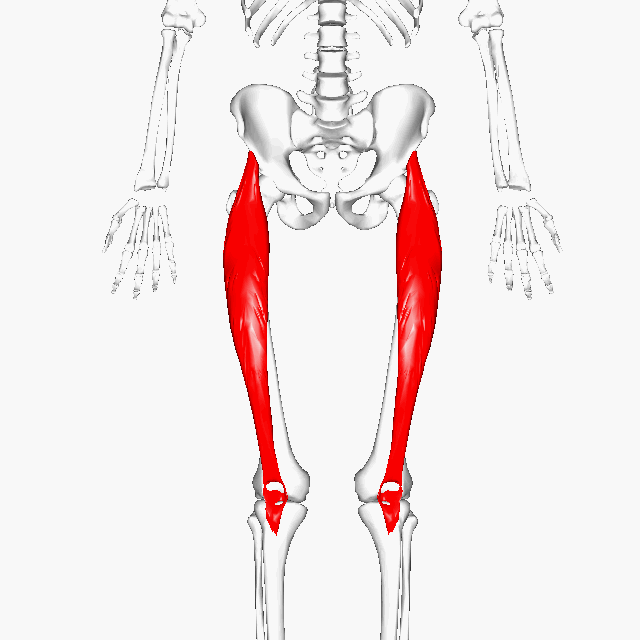

So someone could have kyphosis, they could have lordosis, they could have cervical flexion, whatever it is. If there's a compression happening with the vertebrae and perhaps there's a bulging disc or a herniated disc, then those vertebrae could touch and then it's the same thing as a knee or a hip. And you're going to start getting that soreness and the cracking. And it's the same thing all over again coming from muscle dysfunction. So as posture relates to osteoarthritis in the joints, we're talking about biarticular muscle dysfunction. An example of that could be the rectus femoris. Let's take a look at that.

So you can see the rectus femoris starts at the pelvis and comes all the way down to the top of the tib fib. That means it's crossing two joints, the hip and the knee. This is what we mean by bi-articular muscles. It is directly responsible for stabilizing the knee.

And if this becomes dysfunctional, then that's going to change the alignment of the knee.

I also want to say, I'm just using rectus femoris as an example. There's other bi-articular muscles that cross multiple joints. Muscles are very complicated and if they become dysfunctional, they will misalign you. So now you have a misaligned joint and you're walking through the world.